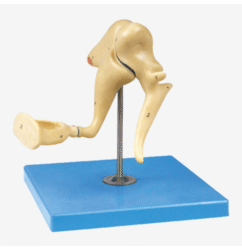

ATL-106 SHOULDER JOINT INTRACAVITARY INJECTION SIMULATOR SOFT

1. Standard anatomical structure, scapula, clavicle, humerus, deltoid, biceps muscle of arm and important ligament of shoulder joint. Train palpation technology of shoulder puncture positioning;

2. Standard position study for puncture and injection;

3. Intelligent evaluation system: the green light on the control box will indicate correct puncture site.

Packing: 1pcs/carton, 48x36x32cm, 6.5kgs